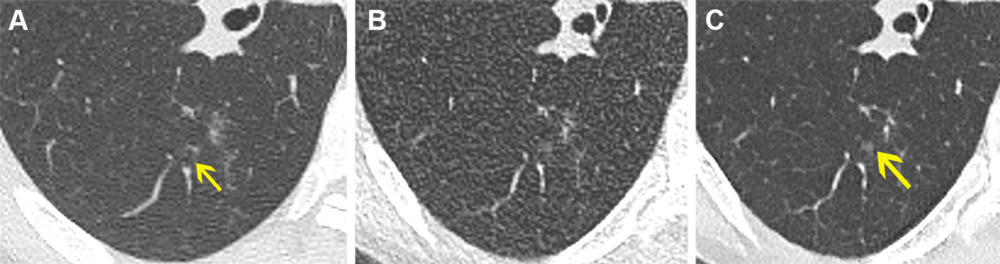

Figure 4. Axial noncontrast chest CT lung window images in a 61-year-old female participant. (A) Normal-dose CT, (B) ultra-low-dose CT (ULDCT), and (C) denoised ULDCT show focal ground-glass opacity (yellow arrow). Ground-glass opacity was correctly identified with both normal- dose CT and denoised ULDCT, but it was missed by both readers at ULDCT due to decreased signal-to-noise ratio.